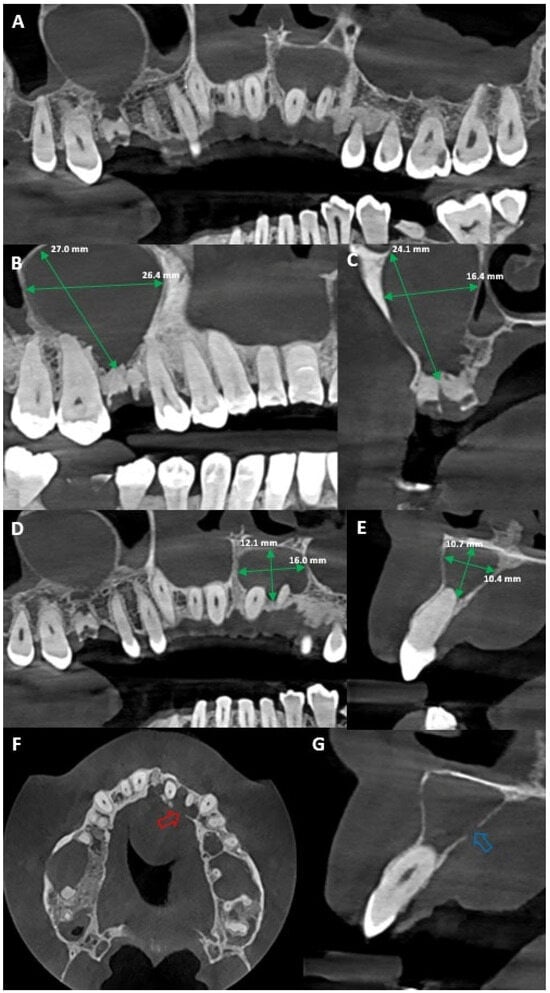

Palatal Abscess of Endodontic Origin with Extensive Radiolucency in Maxillary CBCT Imaging

Marian, D.; Constantin, G.D.; Stana, A.H.; Lile, I.E.; Hajaj, T.; Gag, O.L. Palatal Abscess of Endodontic Origin with Extensive Radiolucency in Maxillary CBCT Imaging. Diagnostics 2025, 15, 2195. https://doi.org/10.3390/diagnostics15172195